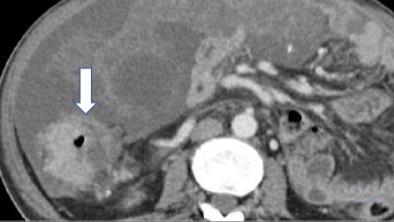

• 计算机体层摄影血管造影在腹腔镜结肠癌根治术前评估中的应用效果

2025, 31(6):24-31. DOI: 10.12235/E20240177

摘要 (181) HTML (147) PDF 4.65 M (171) 评论 (0) 收藏

摘要:目的 分析计算机体层摄影血管造影(CTA)在腹腔镜结肠癌根治术前评估中的应用效果。方法 回顾性分析2021年1月-2024年2月于该院接受腹腔镜结肠癌根治术的120例患者的临床资料。其中,60例行常规腹部CT和CTA,60例行磁共振成像(MRI)。以术后病理为金标准,判断CTA对临床T分期与术后病理的一致性,以及评估肿瘤是否侵犯肠系膜血管和周围组织的准确度。结果 术前CTA诊断T分期的准确率为95.00%(57/60),一致性好(Kappa = 0.925,P < 0.05);术前MRI诊断结肠癌T分期的准确率为98.33%(59/60),两者比较,差异无统计学意义(χ2 = 0.26,P > 0.05)。CTA预判肿瘤是否累及肠系膜上动脉、肠系膜上静脉、肠系膜下动脉、肠系膜下静脉、腹主动脉、肾动脉、肾静脉和脾动脉等血管,与术后病理的一致性好。特别是在预测肠系膜血管受累方面,CTA的敏感度为94.44%,特异度为95.83%,准确度高达95.00%。结论 对于行腹腔镜结肠癌根治术的患者,术前CTA不仅能清晰地显示结肠癌T分期,还能揭示肠系膜血管的走行和变异,以及肿瘤与周围组织的关系和侵犯程度,从而为手术规划提供强有力的支持,确保了腹腔镜手术的安全性,减少了不必要的手术风险。